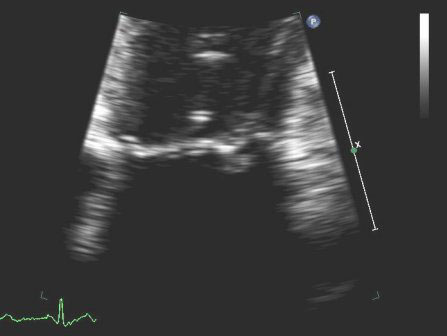

Mitral regurgitation

Posterior mitral valve prolapse on M-mode echo

From the collection of Samir Kapadia and Mehdi H. Shishehbor